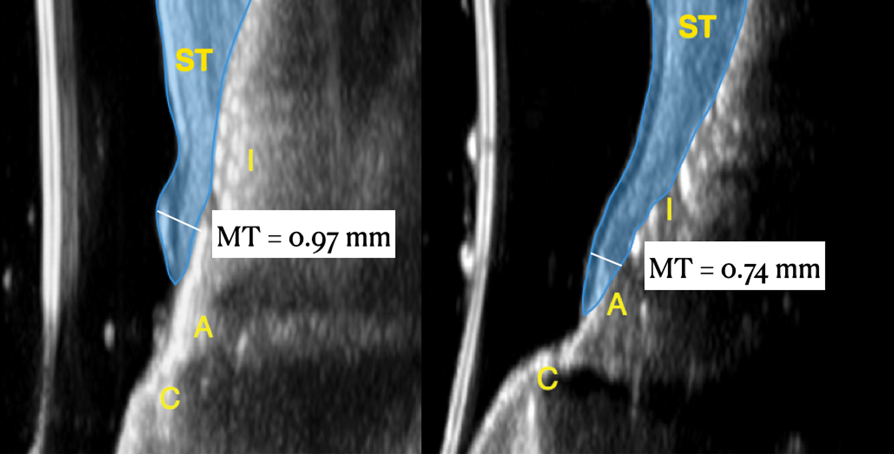

Figure 14 depicts the final outcome at 1 year (which can be compared to the pretreatment photograph in Figure 1). Figure 15 through Figure 18 show clinical comparisons of the outcome at baseline and 1 year, while Figure 19 and Figure 20 provide an ultrasonographic characterization of the soft tissue at baseline and 1 year. The facial probing depths at 1 year were 3-3-3 mm for implant No. 8 and 3-2-3 mm for implant No. 9. The patient was highly satisfied with the esthetic outcomes and overall treatment.

Ultrasonographic Assessment of Mucosal Thickness Gain

Previous studies have described in detail the ultrasound equipment setup and scanning procedures.7,13,15,16 A commercially available ultrasound imaging devicewas used with a 24-MHz miniature-sized transducer to obtain midfacial and interproximal scans at baseline and at 1-year follow-up. The transducer was oriented perpendicular to the occlusal plane and parallel to the implant's long axis to generate "B-mode" grayscale images. B-mode generates 2-dimensional grayscale images in which brightness is the result of the returned echo signal and its strength, which is dependent on the acoustical properties of the periodontal hard- and soft-tissue structures. The scans were saved in digital imaging and communications in medicine (DICOM) files and later exported into a software package, where mucosal thickness was measured 1.5 mm apical to the soft-tissue margin and found to be 0.97 mm and 0.74 mm at the right and left implants, respectively. After 12 months, the respective mucosal thickness was 2.75 mm and 2.48 mm. The soft-tissue thickness gain at the level of the right implant was 1.78 mm for the right implant, and 1.74 mm for the left implant.

This article has described the use of real-time, non-ionizing, high-frequency ultrasonography for assessing the increase in soft-tissue thickness and the anatomy of the peri-implant structures pretreatment and at the 1-year follow-up. The reliability and reproducibility of this technology has been shown in several clinical studies in which ultrasonography also was utilized to assess tissue perfusion after graft procedures and the levels of blood flow at healthy versus diseased implant sites.7,13,15,16,26,27 Ultrasonography enabled the observation of a substantial gain of mucosal thickness at 1 year, with the initial soft tissue (measured 1.5 mm apical to the soft-tissue margin) being 0.97 mm and 0.74 mm at the right and left dental implants, respectively, while the final mucosal thickness was 2.75 mm and 2.48 mm at the right and left dental implants, respectively. Considerable evidence supports the key role augmented gingival thickness plays in the stability of the soft-tissue margin in natural dentition,17,28 and it is reasonable to assume that this concept also may be valid at implant sites.13 The benefits of soft-tissue phenotype modification, in terms of increased keratinized mucosa and mucosal thickness, also include patient-reported outcomes and implant health-related parameters.29

Fig 19. Ultrasonographic comparison of the volumetric gain obtained with the intervention. Fig 19: Baseline. Fig 20: 1-year post-treatment. “C” identifies the crown, “A” the abutment, “I” the implant fixture, and “ST” the soft tissue. The soft tissue at baseline (Fig 19) is highlighted in blue, while the soft tissue at the 1-year follow-up (Fig 20) is shown in purple. Mucosal thickness (“MT”) at baseline (Fig 19) and at 1 year (Fig 20) is also displayed. (In both figures, the left panel is implant No. 8 midfacial, and the right panel is implant No. 9 midfacial.)

Figure 19

Fig 20. Ultrasonographic comparison of the volumetric gain obtained with the intervention. Fig 19: Baseline. Fig 20: 1-year post-treatment. “C” identifies the crown, “A” the abutment, “I” the implant fixture, and “ST” the soft tissue. The soft tissue at baseline (Fig 19) is highlighted in blue, while the soft tissue at the 1-year follow-up (Fig 20) is shown in purple. Mucosal thickness (“MT”) at baseline (Fig 19) and at 1 year (Fig 20) is also displayed. (In both figures, the left panel is implant No. 8 midfacial, and the right panel is implant No. 9 midfacial.)

Figure 20